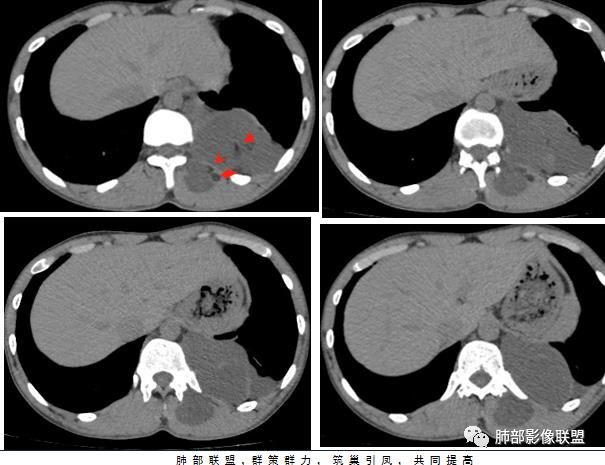

杨泽锋:

有钙化、有脂肪,首先考虑畸胎瘤;多空间病变,需要和神经纤维瘤病鉴别

王江涛:

左后纵隔不规则多房囊状液性密度灶,边界清楚,伴钙化,见缝就钻,考虑良性,囊性淋巴管瘤可能性大

任广国:

左侧后纵隔及胸腔多房性囊性肿物,其内可见脂肪,边缘可见蛋壳状钙化,胸壁侧肌肉内病变范围小,考虑囊性畸胎瘤,伴局部破裂可能。鉴别结核(肌肉内冷脓肿范围太小)

红星:

左脊柱旁、胸壁及竖脊肌多发肿物,有坏死囊变、钙化,平均CT值有-21一-3,肿物张力较大,钙化位于周围,象包膜的钙化。考虑结核性?畸胎瘤?血肿机化?

徐飞:

左后纵隔不规则形多房占位,边界清楚,沿纵轴生长,蛋壳样钙化,能见少许脂肪密度,竖脊肌受累。近期感觉长大,囊性畸胎瘤恶变?

群锋:

左脊柱旁囊性肿块,皮样囊肿可能,鉴别包虫囊肿,神经源性肿瘤囊变